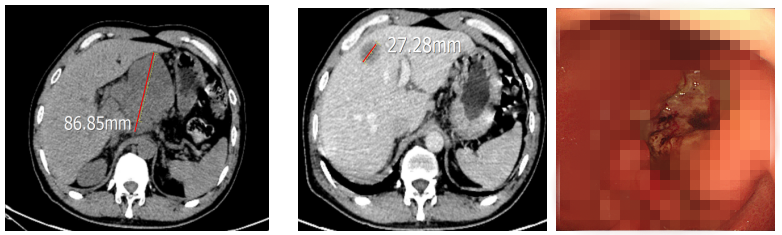

文某因“腹部胀痛”2021年10月就诊于化疗科,胃镜示:胃溃疡恶变(胃窦)。病理及免疫组化结果示:低分化腺癌,C-erbB-2(-),Ki-67(阳性率约70%)。胸腹部CT提示:肝胃间隙淋巴结转移(约8.2×5.6cm);肝内多发转移(约1.5cm);左侧颈根部转移淋巴结(约2.3*1.7cm)。

治疗前腹部CT及胃镜